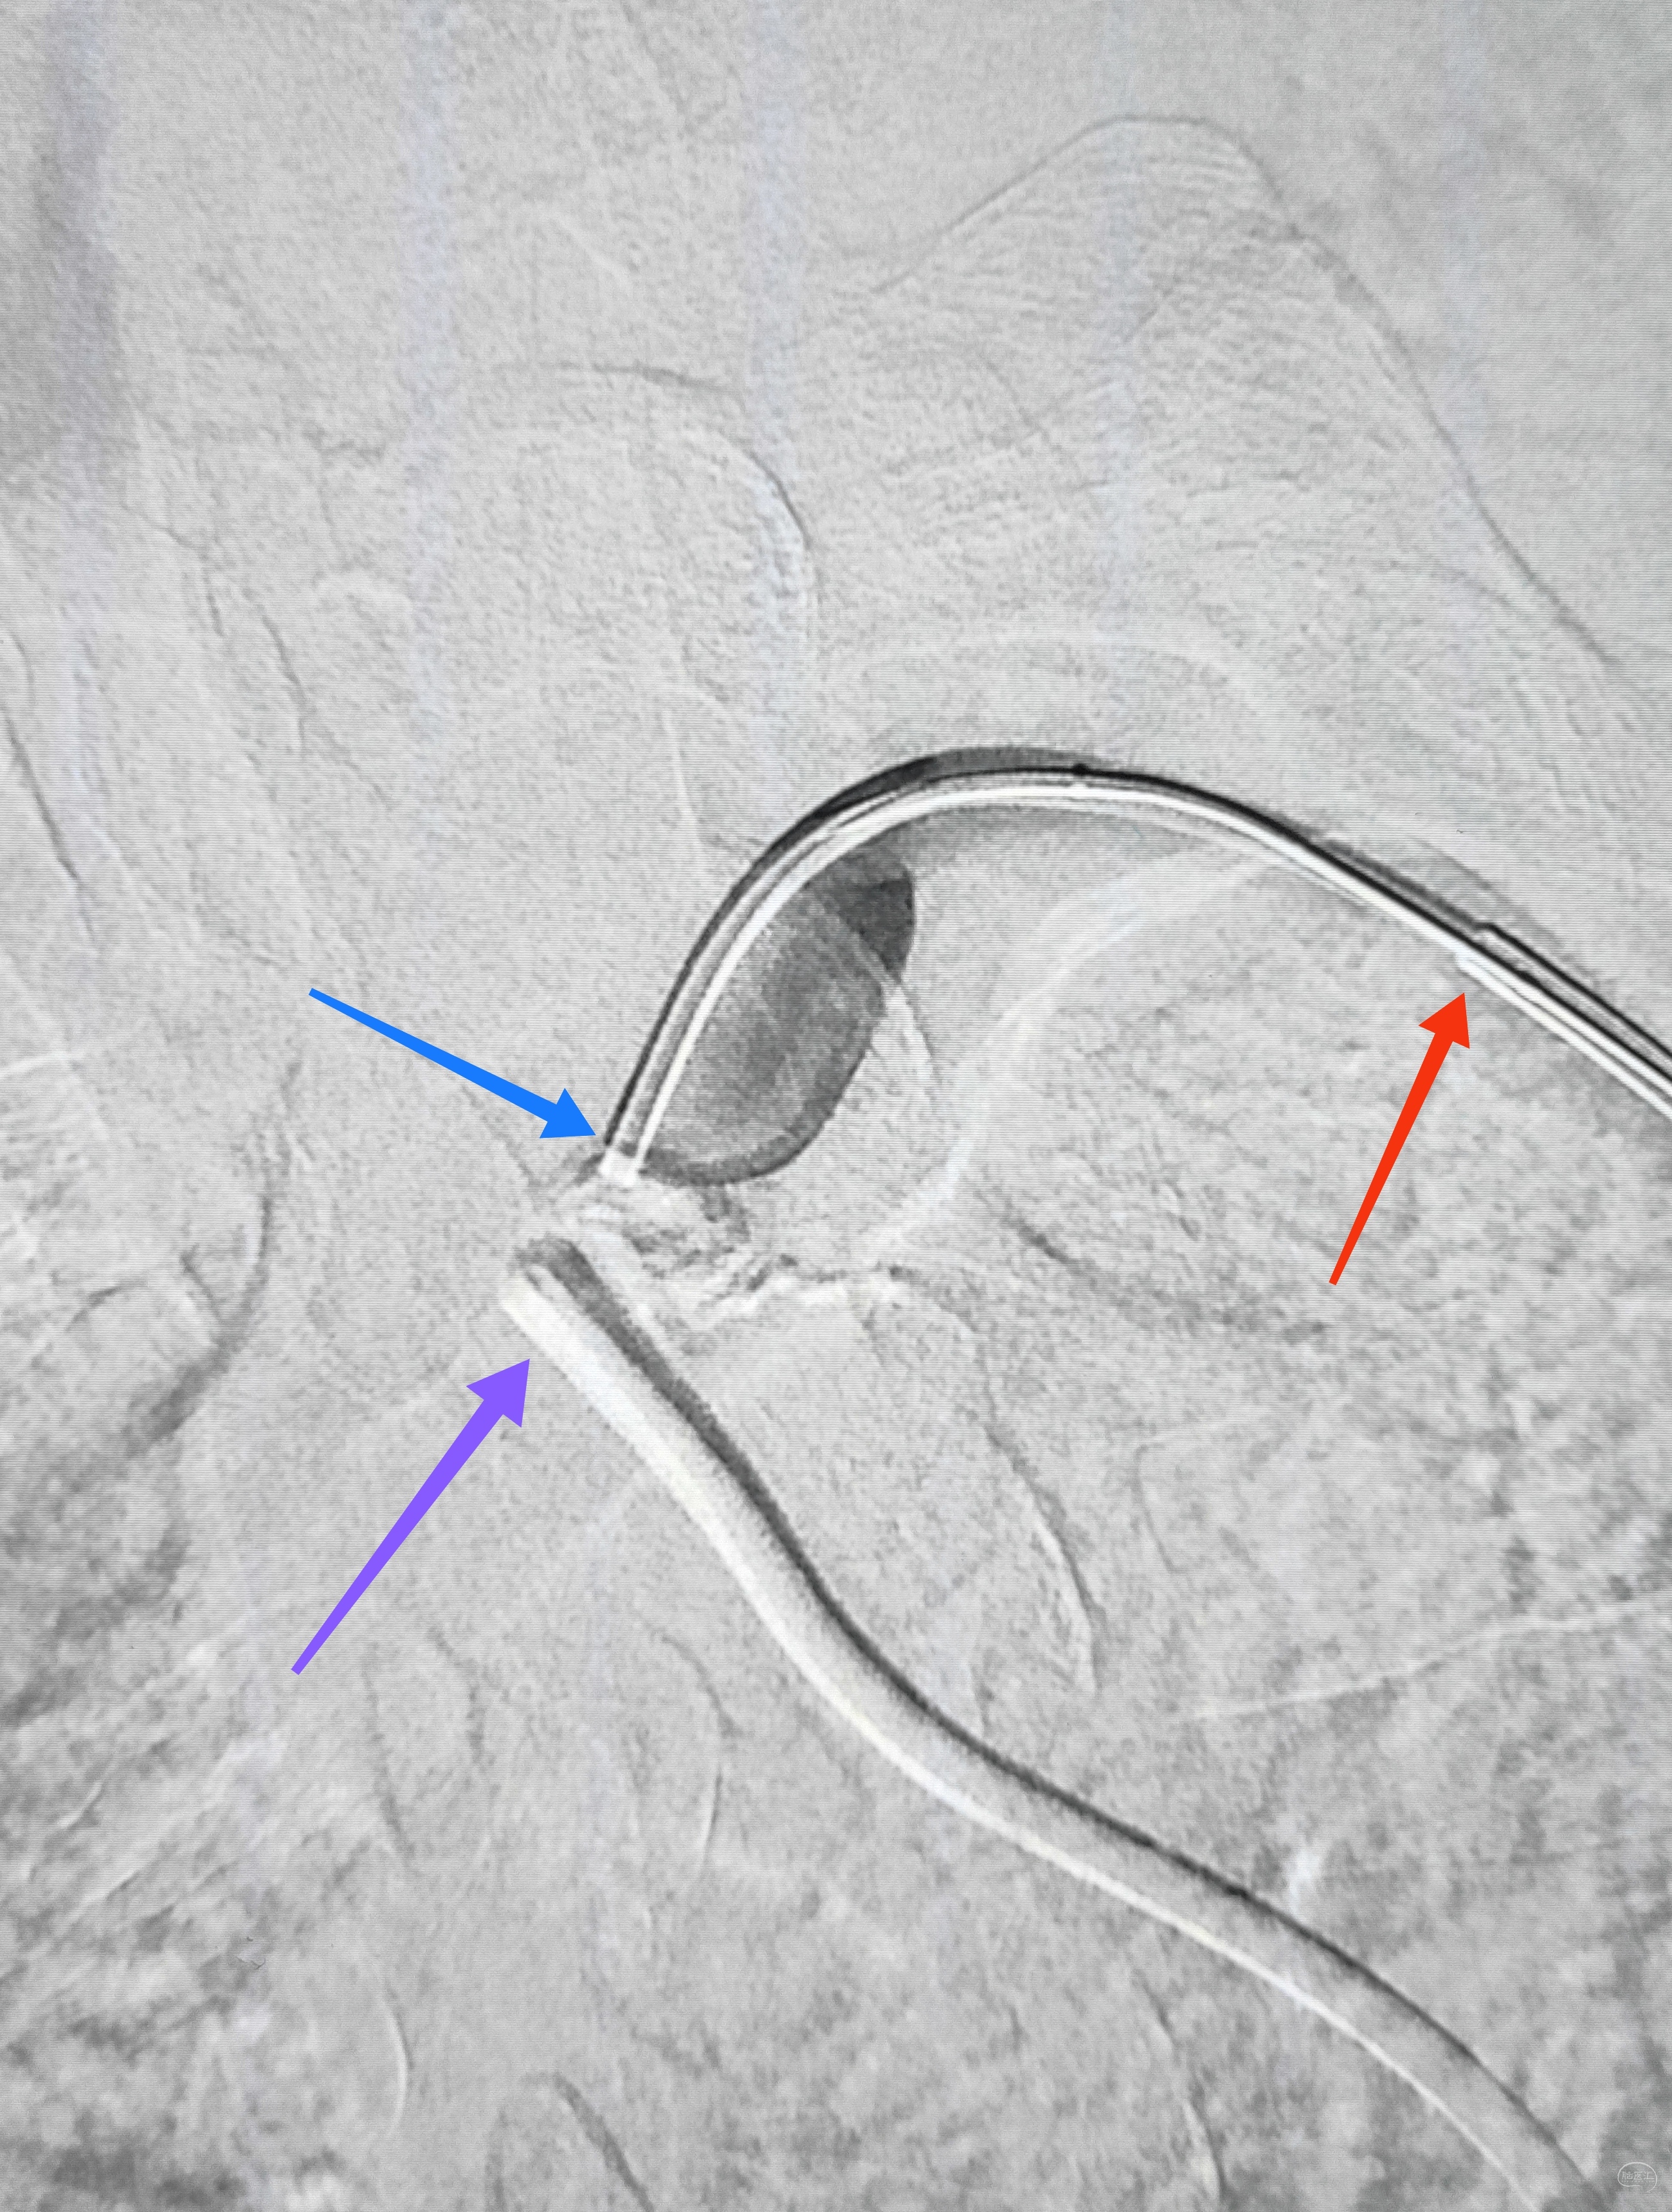

一切看似理想,一切看似简单,诡异的事情还是发生了,8F导引导管死活无法进入左侧锁骨下动脉,各种方法尝试个遍:泥鳅走远,单弯挂口,Sim挂口,屡战屡败(水平退步明显,不应该啊,夹层?),因为怕折腾,因为想安全,怕进假腔,弄出夹层。索性换一个思路:空中接力,构建桡-股动脉大环线

自下向上走不通,那就从上边来

经左侧桡动脉6F导引导管,出加长泥鳅,一路向下,逼近右侧股动脉鞘

以为很难,其实不然,泥鳅头段顺利进入股动脉鞘内,但是问题来了,因为是动脉鞘,有活瓣封口,泥鳅无法逆向穿过动脉鞘入口,何解?

那就利用换鞘技术,桡动脉侧持续给泥鳅张力并顶住(助手),缓慢回撤股动脉鞘至体外(主刀),看到泥鳅后抓紧,后拽;长度足够后,带套管重新置入8F股动脉鞘,完成桡-股动脉大环线建立。

泥鳅两段露头,8F导引导管沿泥鳅攀爬,一把干到左侧肱动脉为止